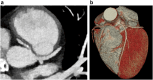

Methods and results: Even in recent Italian history, unexpected deaths continue to affect athletes but surprisingly any real knowledge regarding the numbers and the impact of those tragedies must take medical literature and non-medical press into consideration. Herein we report the clinical case of a 13-year-old patient with a bicuspid aortic valve, whose mother was alarmed by the news of a young boy who died because of an anomalous origin of coronary artery (AOCA) which had not been diagnosed at transthoracic echocardiography (TTE). Her obstinacy induced the physicians to repeat TTE and led to the same diagnosis in her son: actually, his right coronary artery originated from the opposite sinus of Valsalva. The suspicion was confirmed by coronary CT scan and, thanks to appropriate therapy, the boy now fares well.

Conclusions: AOCA is the second most common cause of sudden death in young athletes. Although AOCA is often undetectable at ECG, TTE increases sensitivity of preparticipation screening. It could therefore allow us to avoid such coincidences and prevent sudden juvenile death.